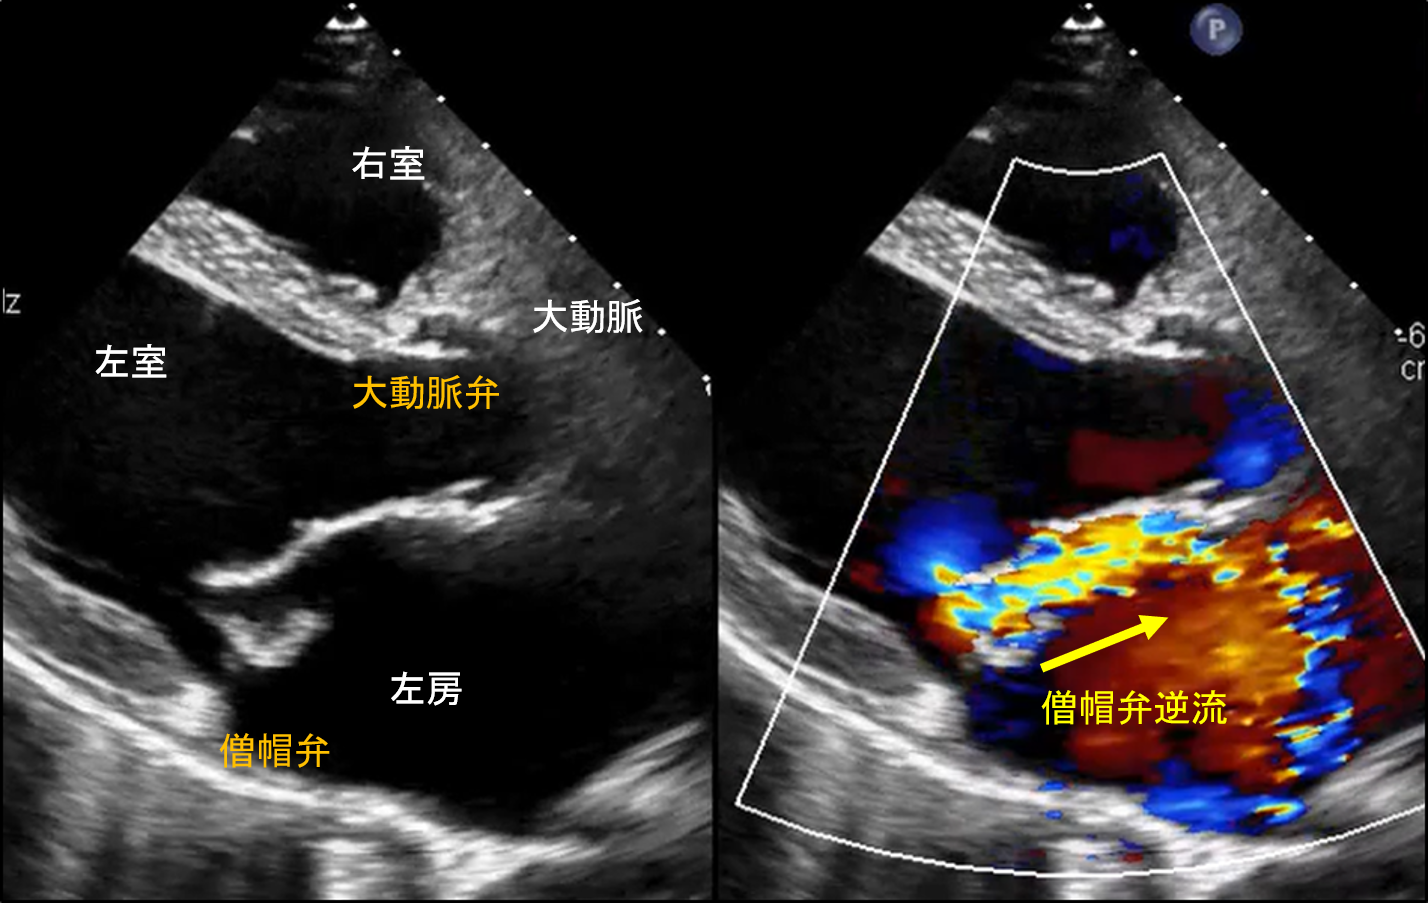

図1:左房粘液腫のCT所見・エコー所見